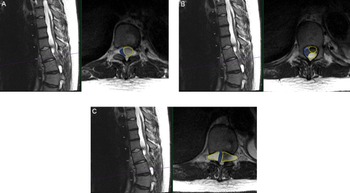

A 15-year-old male with MFS, scoliosis, and an extensive surgical history involving his thoracoabdominal aorta presented with a 9-month history of imbalance. He had myelopathy with right leg pain/weakness eventually requiring assistance for walking. His examination was remarkable for hyperreflexia and inability to tandem walk along with loss of proprioception. Magnetic resonance imaging (MRI) spine revealed thoracic DE and tethering of the spinal cord at T9-L1 with multilevel loculated cysts causing compression from the thoracic cord to the conus causing a 2-mm width cord at T10/T11 (Figure 1). He was admitted to the Pediatric Intensive Care Unit (PICU) for preoperative anticoagulation bridging due to his mechanical valves.

Figure 1: Preoperative findings of multiloculated intradural spinal cysts on T2-weighted axial and sagittal thoracic MRI (A) at T10 level with compression of the cord (blue outline) to the right due to large cyst on the left (yellow outline); (B) at superior T11 level with two large left-sided cysts (yellow outlines) compressing the cord to the right (blue outline); and (C) at T11/12 level with the cord compressed by bilateral loculated cysts (yellow outlines) to a diameter of 2 mm in the cord (blue outline).